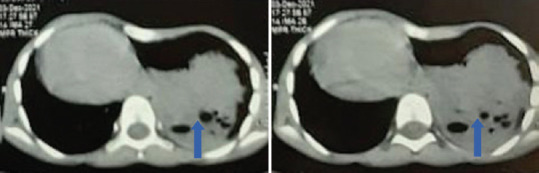

肺动脉闭塞症和囊性肺腺瘤样畸形是罕见的先天性肺囊性疾病。因此,在同一个人身上同时出现这两种疾病的情况非常罕见。肺封闭是一种无功能的肺组织肿块,其血液供应来自肺循环以外的全身血液供应。先天性囊性肺腺瘤样畸形是一种由异常支气管气室和功能性肺泡缺乏组成的肿块。本病例报告了一名 9 岁女孩的病例,她在过去 15 天里出现间歇性发热、左侧胸痛和咳嗽,并且自孩提时代起就反复咳嗽,这提示她患有混合性肺动脉栓塞、先天性肺囊样腺瘤畸形和右心室突出症。

Pulmonary sequestration and cystic pulmonary adenomatoid malformation are rare congenital cystic disorders of the lungs. The presence of both the diseases in the same individual is therefore very uncommon. Pulmonary sequestration is a nonfunctional pulmonary tissue mass that derives its blood supply from systemic blood supply other than pulmonary circulation. Congenital cystic pulmonary adenomatoid malformation represents a mass consisting of abnormal bronchiolar air spaces and a deficiency of functional alveoli. This is the case report of a 9-year-old girl with intermittent fever, left-sided chest pain, and cough for the past 15 days along with recurrent coughs since childhood suggestive of hybrid pulmonary sequestration, congenital cystic adenomatoid malformation, and dextrocardia.